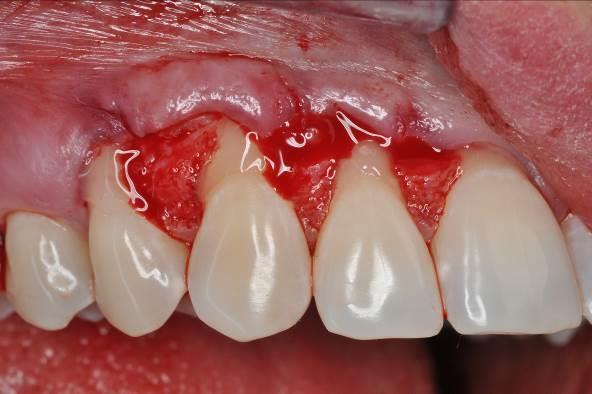

02/06 - Oblique incisions according to the modified coronally advanced flap technique (Zucchelli & De Sanctis J Periodontol. 2000).Multiple gingival recessions treated with the modified coronally advanced flap in conjunction with mucoderm® and Straumann® Emdogain® - Dr. D. B. Hangyási